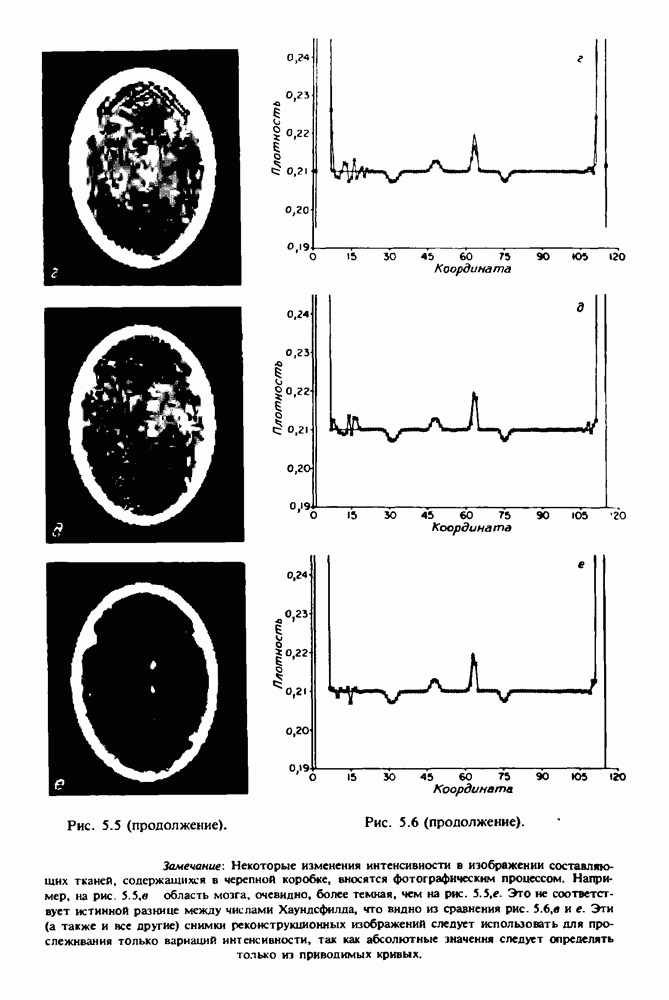

15.5. ЭКСПЕРИМЕНТАЛЬНЫЕ РЕЗУЛЬТАТЫ

Наш первый пример относится к случаю отображения системы желудочков головного мозга человека, которое было сделано по восьми смежным срезам толщиной На рис. 15.1 (вверху) приведены фрагменты из 80 х 80 элементов изображения трех из указанных срезов. Система желудочков изображена на фрагментах полностью. Размер элемента изображения в срезах составлял 1,5 х 1,5 мм, что соответствовало размеру элементарного

объема 1,5 х 1,5 х 8 мм, хотя более желательна, как и в предыдущих разделах, была бы кубическая форма элементарных объемов. Чтобы преобразовать элементарные объемы в кубические, использовалась линейная интерполяция данных для оценки 38 смежных срезов толщиной 1,5 мм. Таким образом, формируется массив из 80 х 80 х 32 чисел, характеризующих среднюю плотность множества элементарных объемов кубической формы.

Причина, по которой желудочки мозга выглядят более темными, чем окружающие ткани, состоит в том, что они содержат спинномозговую жидкость с несколько меньшим, чем у мозга, линейным коэффициентом ослабления (табл. 4.1). Поэтому диапазон значений, введенный в разд. 15.1, оказался таким, что его верхний предел стал больше, чем линейный коэффициент ослабления цереброспинальной жидкости, но меньшим, чем для самого мозга. Последнее означает, что все элементарные объемы, характеризующие спинномозговую жидкость, имеют числа Хаунсфилда в указанном диапазоне Таким образом, множество элементарных объемов, в которых числа Хаунсфилда лежат в диапазоне (разд. 15.2), содержит не только области желудочков, но также и другие части мозга, либо заполненные спинномозговой жидкостью, либо не заполненные ей, но имеющие по разным причинам такие же числа Хаунсфилда в данном диапазоне, например, вследствие наличия шума в исходных данных, артефактов при реконструкции и т.д. Элементарные объемы, которые принадлежат множеству изображены в виде светлых областей в нижней части рис. 15.1. Анатомическая картина соответствующих частей системы желудочков, показывающая в том числе положение corpora quadragemina («четверохолмие»), приведена на рис. 15.6.

Рис. 15.6. Анатомическая структура фрагмента системы желудочков головного мозга человека. 1 — передние рога латерального желудочка; 2 — третий желудочек; 3 — четверохолмие; 4 — задние рога латерального желудочка.

Рис. 15.7. (см. скан) Трехмерные проекции зарегистрированной поверхности системы желудочков головного мозга человека.

Для формирования трехмерного изображения системы желудочков (рис. 15.7) были использованы все рассмотренные в трех предыдущих разделах операции определения границ органов, исключения скрытых их частей поверхности и наложения теней. Число зарегистрированных граничных граней для системы желудочков составляло 8970, при этом регистрация множества из 80 х 80 х 38 элементарных объемов требует менее 0,5 мин машинного времени (на мини-ЭВМ типа Eclipse S/200).